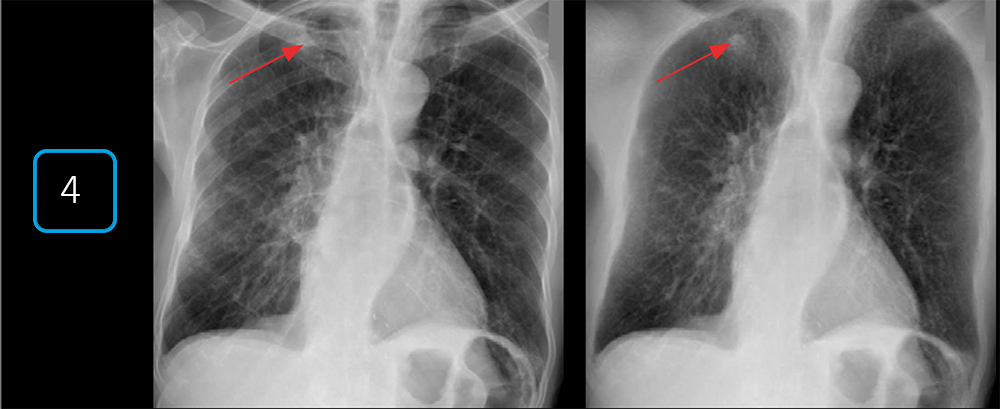

- Автоматическая сшивка снимков

Для изучения протяженных зон (весь позвоночник, нижние конечности) система автоматически делает серию кадров и объединяет их в единое панорамное изображение без швов. Это обеспечивает высокую точность измерений при диагностике сколиоза или планировании операций на суставах.